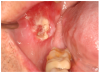

Mucosal lesions are characterized by three main signs: 1) lichenoid inflammation, 2) erythema, and 3) ulcerations.20 Lichenoid inflammation appears as white reticular streaks or lacey lines that resemble Wickham striae observed in oral lichen planus and are considered to be a diagnostic feature of oral cGVHD7,30 (Figure 1a). While these lesions may occur anywhere in the oral cavity, they most frequently appear on the buccal mucosa and tongue.31,32 Lichenoid lesions may be accompanied by varying degrees of erythema and ulceration, which are features often associated with more severe symptoms (Figure 1b-c). Ulcerations represent a breakdown in oral mucosa and can be particularly symptomatic, limiting functions such as oral nutrition, speech, and oral hygiene maintenance.33

Figure 1a. Lichenoid inflammation

Figure 1a

Figure 1b. Lichenoid erythema

Figure 1b